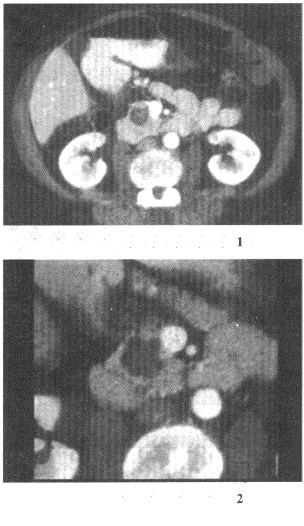

女,57歲,上腹部隱痛半年余,CT檢查如圖

12.最可能的診斷是

正確答案:12.D;13.A;14.A 解題思路:可見(jiàn)增強(qiáng)掃描腫塊內(nèi)呈蜂窩狀結(jié)構(gòu),為胰腺囊腺瘤的特點(diǎn)。